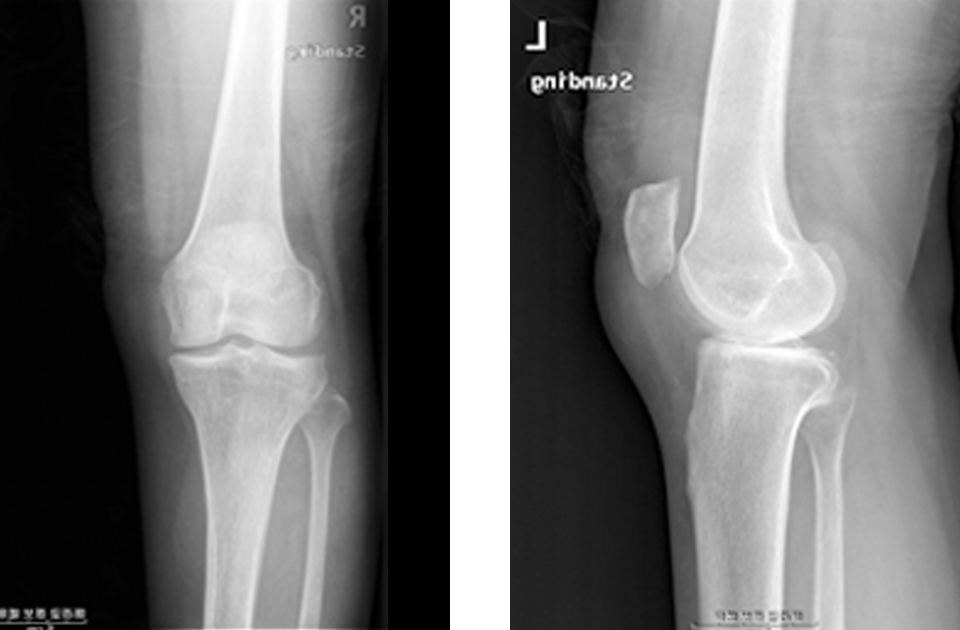

휜다리 교정술 치료 사례

- 환자 동의하에 게시된 이미지입니다.

<수술전 엑스레이 사진>

<수술후 엑스레이 사진>